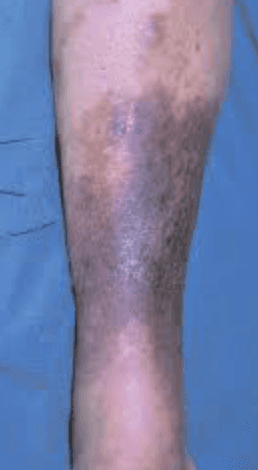

Es importante saber que después de una TVP en MM.II. , dependiente de la zona y la amplitud de la trombosis, va a quedar una secuela que da lugar a lo que llamamos SÍNDROME POSTFLEBÍTICO O POSTROMBÓTICO. Esto quiere decir que va a quedar una Insuficiencia Venosa Crónica caracterizada por la aparición de edema ,pesadez, inflamación dérmica e incluso con el tiempo dar lugar a alteraciones de la piel (hipodermis, eczema, celulitis esclerosa o úlceras).

SINDROME POSTFLEBÍTICO AVANZADO

Después ése una Trombosis Venosa Profunda (TVP) en los miembros inferiores se produce un edema continuado de la pierna afecta; es una secuela normal y variable en su evolución que tenemos los Cirujanos Vasculares que valorar y tratar para evitar que lleguen, con el tiempo, a producir lesiones de la piel que pueden ser muy incapacitares.